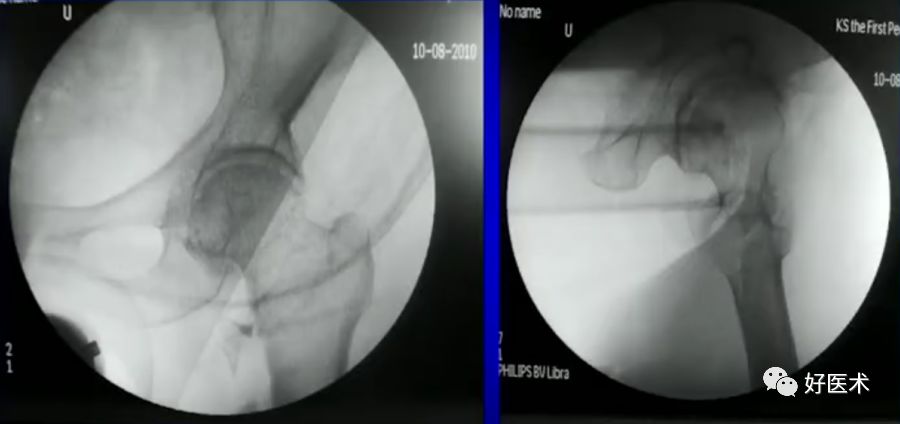

6.正确的股骨颈正侧位

侧卧位如何透股骨颈的侧位:

-

标准侧位

球管20-30°

侧卧位行转子间骨折固定

病例:男,34岁,高处坠落伤,仅骨折余正常

处理方法:

髓内钉(开放VS闭合)

钢板

其他

术前牵引

开口、定位

术中过程